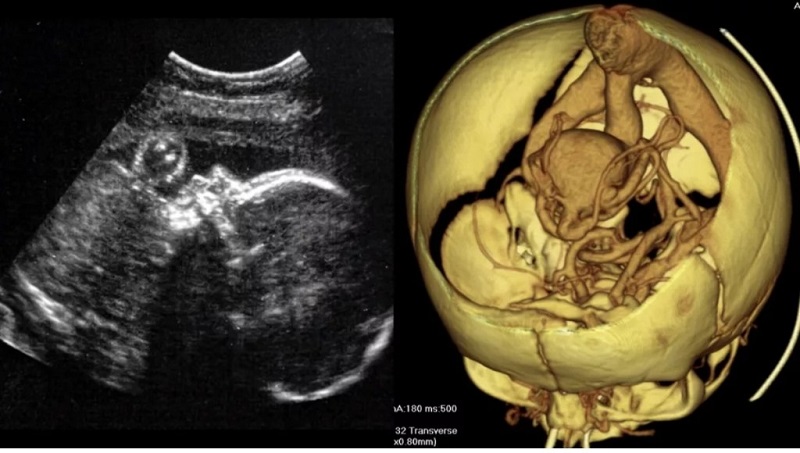

cta检查▲ct检查颅内动脉瘤是颅内血管壁的局部膨隆,通俗的说,就是